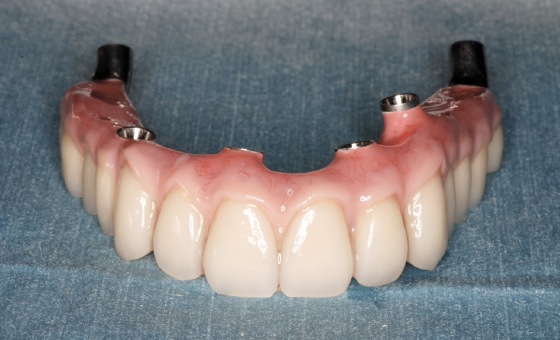

人工歯はネジでインプラントに固定してありますので、万が一破損などの場合でも、専用のドライバーで外して修理が可能です。

オールオン4では、失われた歯茎も人工的に作りますので、お口の張りも回復させることができ、自然な美しい笑顔を作ることができます。